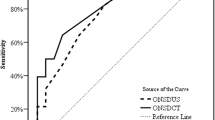

The ONSDI, ONSDI-OND, and ONSDI/ETD were positively associated with ICP (r = 0.455, 0.482, 0.423 and p = 0.001, < 0.001, 0.002, respectively), whereas the WCC was negatively associated with ICP (r = − 0.586, p < 0.001). The WCC showed the highest predictive power for increased ICP (area under the receiver operating characteristic curve [AUC] = 0.904), whereas the ONSDI-OND and ONSDI also presented with acceptable predictive power among the ONSD-related parameters (AUC = 0.831, 0.803, respectively). The cutoff values for increased ICP prediction for ONSDI, ONSDI-OND, and WCC were 6.29, 3.03, and 3.68 mm, respectively. The AUC of the combination of ONSDI-OND and WCC was 0.952 (95% confidence interval 0.896–1.0, p < 0.001).

The receiver operating characteristic curve for the WCC showed that it remarkably differentiated increased ICP from normal ICP, with an AUC of 0.904 (sensitivity 85.7%, specificity 86.7%; Fig. 4, Table 2). Among the ONSD-related parameters, ONSDI and ONSDI-OND also presented great predictive power, with the latter (AUC = 0.831) slightly outperforming the former (AUC = 0.803). The combination of ONSDI-OND and WCC had the greatest discriminability between normal and elevated ICP, with an AUC of 0.952 (95% confidence interval 0.896–1.0, p < 0.001, Fig. 4, Table 2). The cutoff values for predicting increased ICP for ONSDI, ONSDI-OND, and WCC were 6.29, 3.03, and 3.68 mm, respectively.

ROC curve analysis of the predictive power of the WCC and combination (left). ROC curve analysis of the predictive power of the ONSD-related parameters including the ONSDI-OND, ONSDI, and ONSDI/ETD (right). AUC area under the receiver operating characteristic curve, ONSD optic nerve sheath diameter, ONSDI/ETD the ratio of the ONSD including the dura mater and the eyeball transverse diameter, ONSDI-OND the difference between the ONSD including the dura mater and the optic nerve diameter, ROC receiver operating characteristic, WCC width of the crural cistern